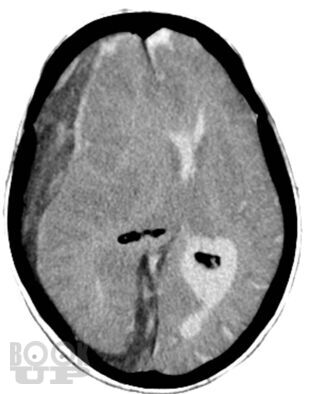

Учебное пособие написано в соответствии с основной профессиональной образовательной программой — программой подготовки кадров высшей квалификации в ординатуре по специальности 31.08.56 «Нейрохирургия». Издание содержит 144 ситуационные задачи. В задачах приводятся клинические случаи по всем разделам программы, в том числе рассматриваемые на смежных с нейрохирургией дисциплинах. Особое внимание уделено клиническим примерам, иллюстрирующим основные неотложные состояния у пациентов и раненых нейрохирургического профиля.

Ситуационные задачи составлены с целью обучения ординаторов методике диагностики травм и заболеваний нервной системы; также они могут быть актуальными и для практикующих нейрохирургов в качестве справочного пособия, в котором приведены алгоритмы диагностики и стандарты оказания помощи при наиболее распространенных нейрохирургических заболеваниях и травмах.